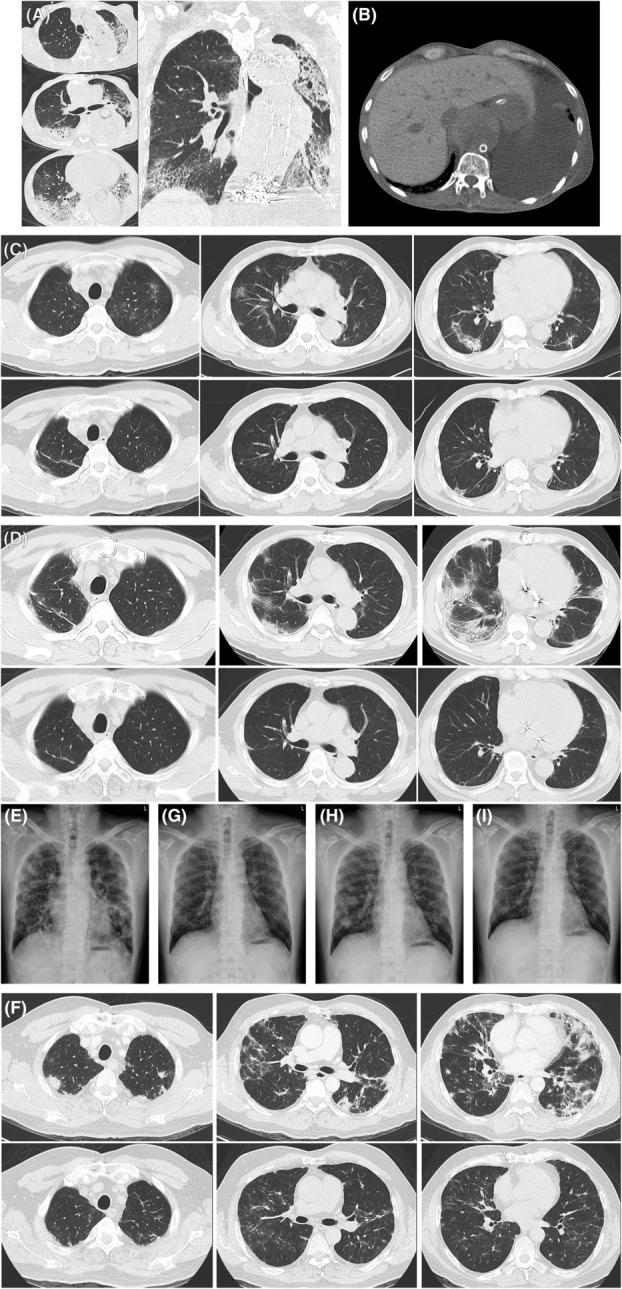

Variable radiographic and histologic presentations of amiodarone-related interstitial lung disease and the importance of avoiding re-exposure.

Amiodarone is a commonly used antiarrhythmic agent but exhibits potential pulmonary toxicity. In this case series, we describe the clinical, radiographic, and histologic manifestations of three patients who developed interstitial lung disease (ILD) following amiodarone treatment for variable lengths of time with different dosages. The presentations on computed tomographic images and in pulmonary pathology differed among the three patients. All three had immediate discontinuation of amiodarone and received treatment with systemic corticosteroids. One patient eventually died from ventilator-associated pneumonia after an initial improvement. The other two patients recovered well but later experienced ILD recurrence following brief re-exposure to amiodarone. Through this case series, we aim to demonstrate the variable features of amiodarone-related ILD, and highlight the importance of timely amiodarone cessation and avoiding re-exposure to prevent the progression and recurrence of ILD.